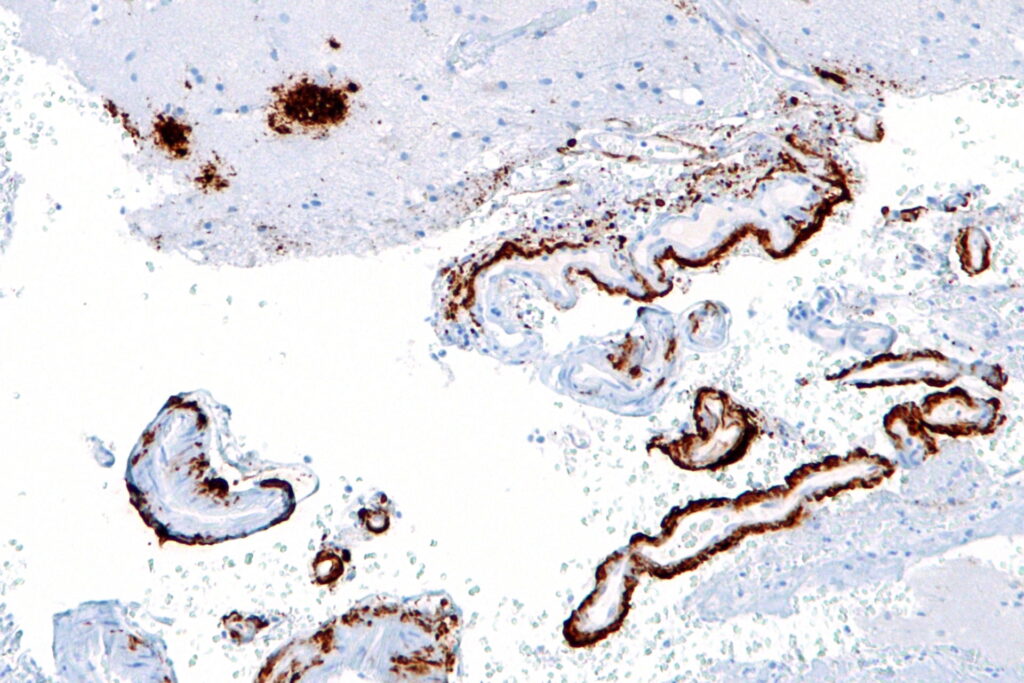

アミロイドβは脳細胞の外側に粘着性のプラーク(しこり)を形成し、神経細胞間の通信を妨げるとされています。

このようなアミロイド斑と神経原線維変化は、アルツハイマー病の特徴的な所見として知られています。

蛍光測定器や電子顕微鏡による観察の結果、CagANを添加したサンプルではアミロイドβの凝集が大幅に抑制されていたのです。

さらに、核磁気共鳴(NMR)法を使って、CagANとアミロイドβの相互作用を可視化したところ、分子レベルでタンパク質の結合を妨げている様子が明らかになりました。